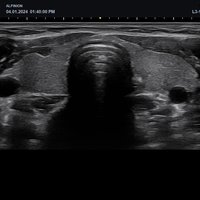

• Endokavitär-Sonden

• VE3-10H (3-10 MHz) für Ultraschalluntersuchungen in den Bereichen Geburtshilfe, Gynäkologie, Urologie

• EV3-10T gekrümmt (3-10 MHz) für Ultraschalluntersuchungen in den Bereichen Geburtshilfe, Gynäkologie, Urologie

• EC3-10T gerade (3-10 MHz) für Ultraschalluntersuchungen in den Bereichen Geburtshilfe, Gynäkologie, Urologie